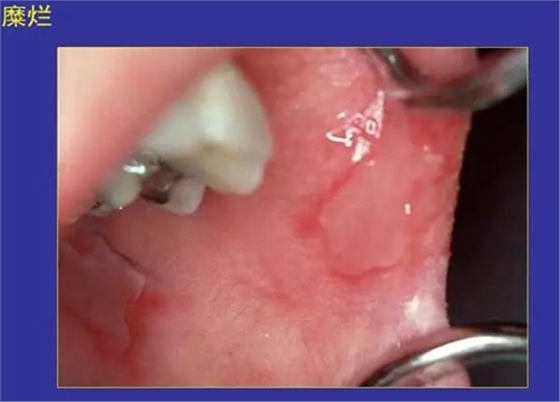

5.糜爛:黏膜表淺缺損,不損及基底細胞層。

正常口腔黏膜及常見病損圖

正??谇火つぜ俺R姴p圖